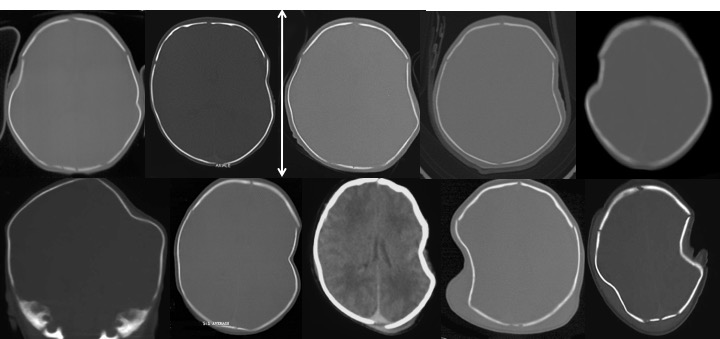

l’os du nouveau-né est élastique. comme illustré ci-dessus, il existe 2 positions d’équilibre, la bonne en convexité, la mauvaise en embarrure. les propriétés mécaniques de la voûte découlent de l’élasticité de l’os, de sa forme et de la taille de l’embarrure. c’est pourquoi une embarrure de petite taille ne perdure pas.